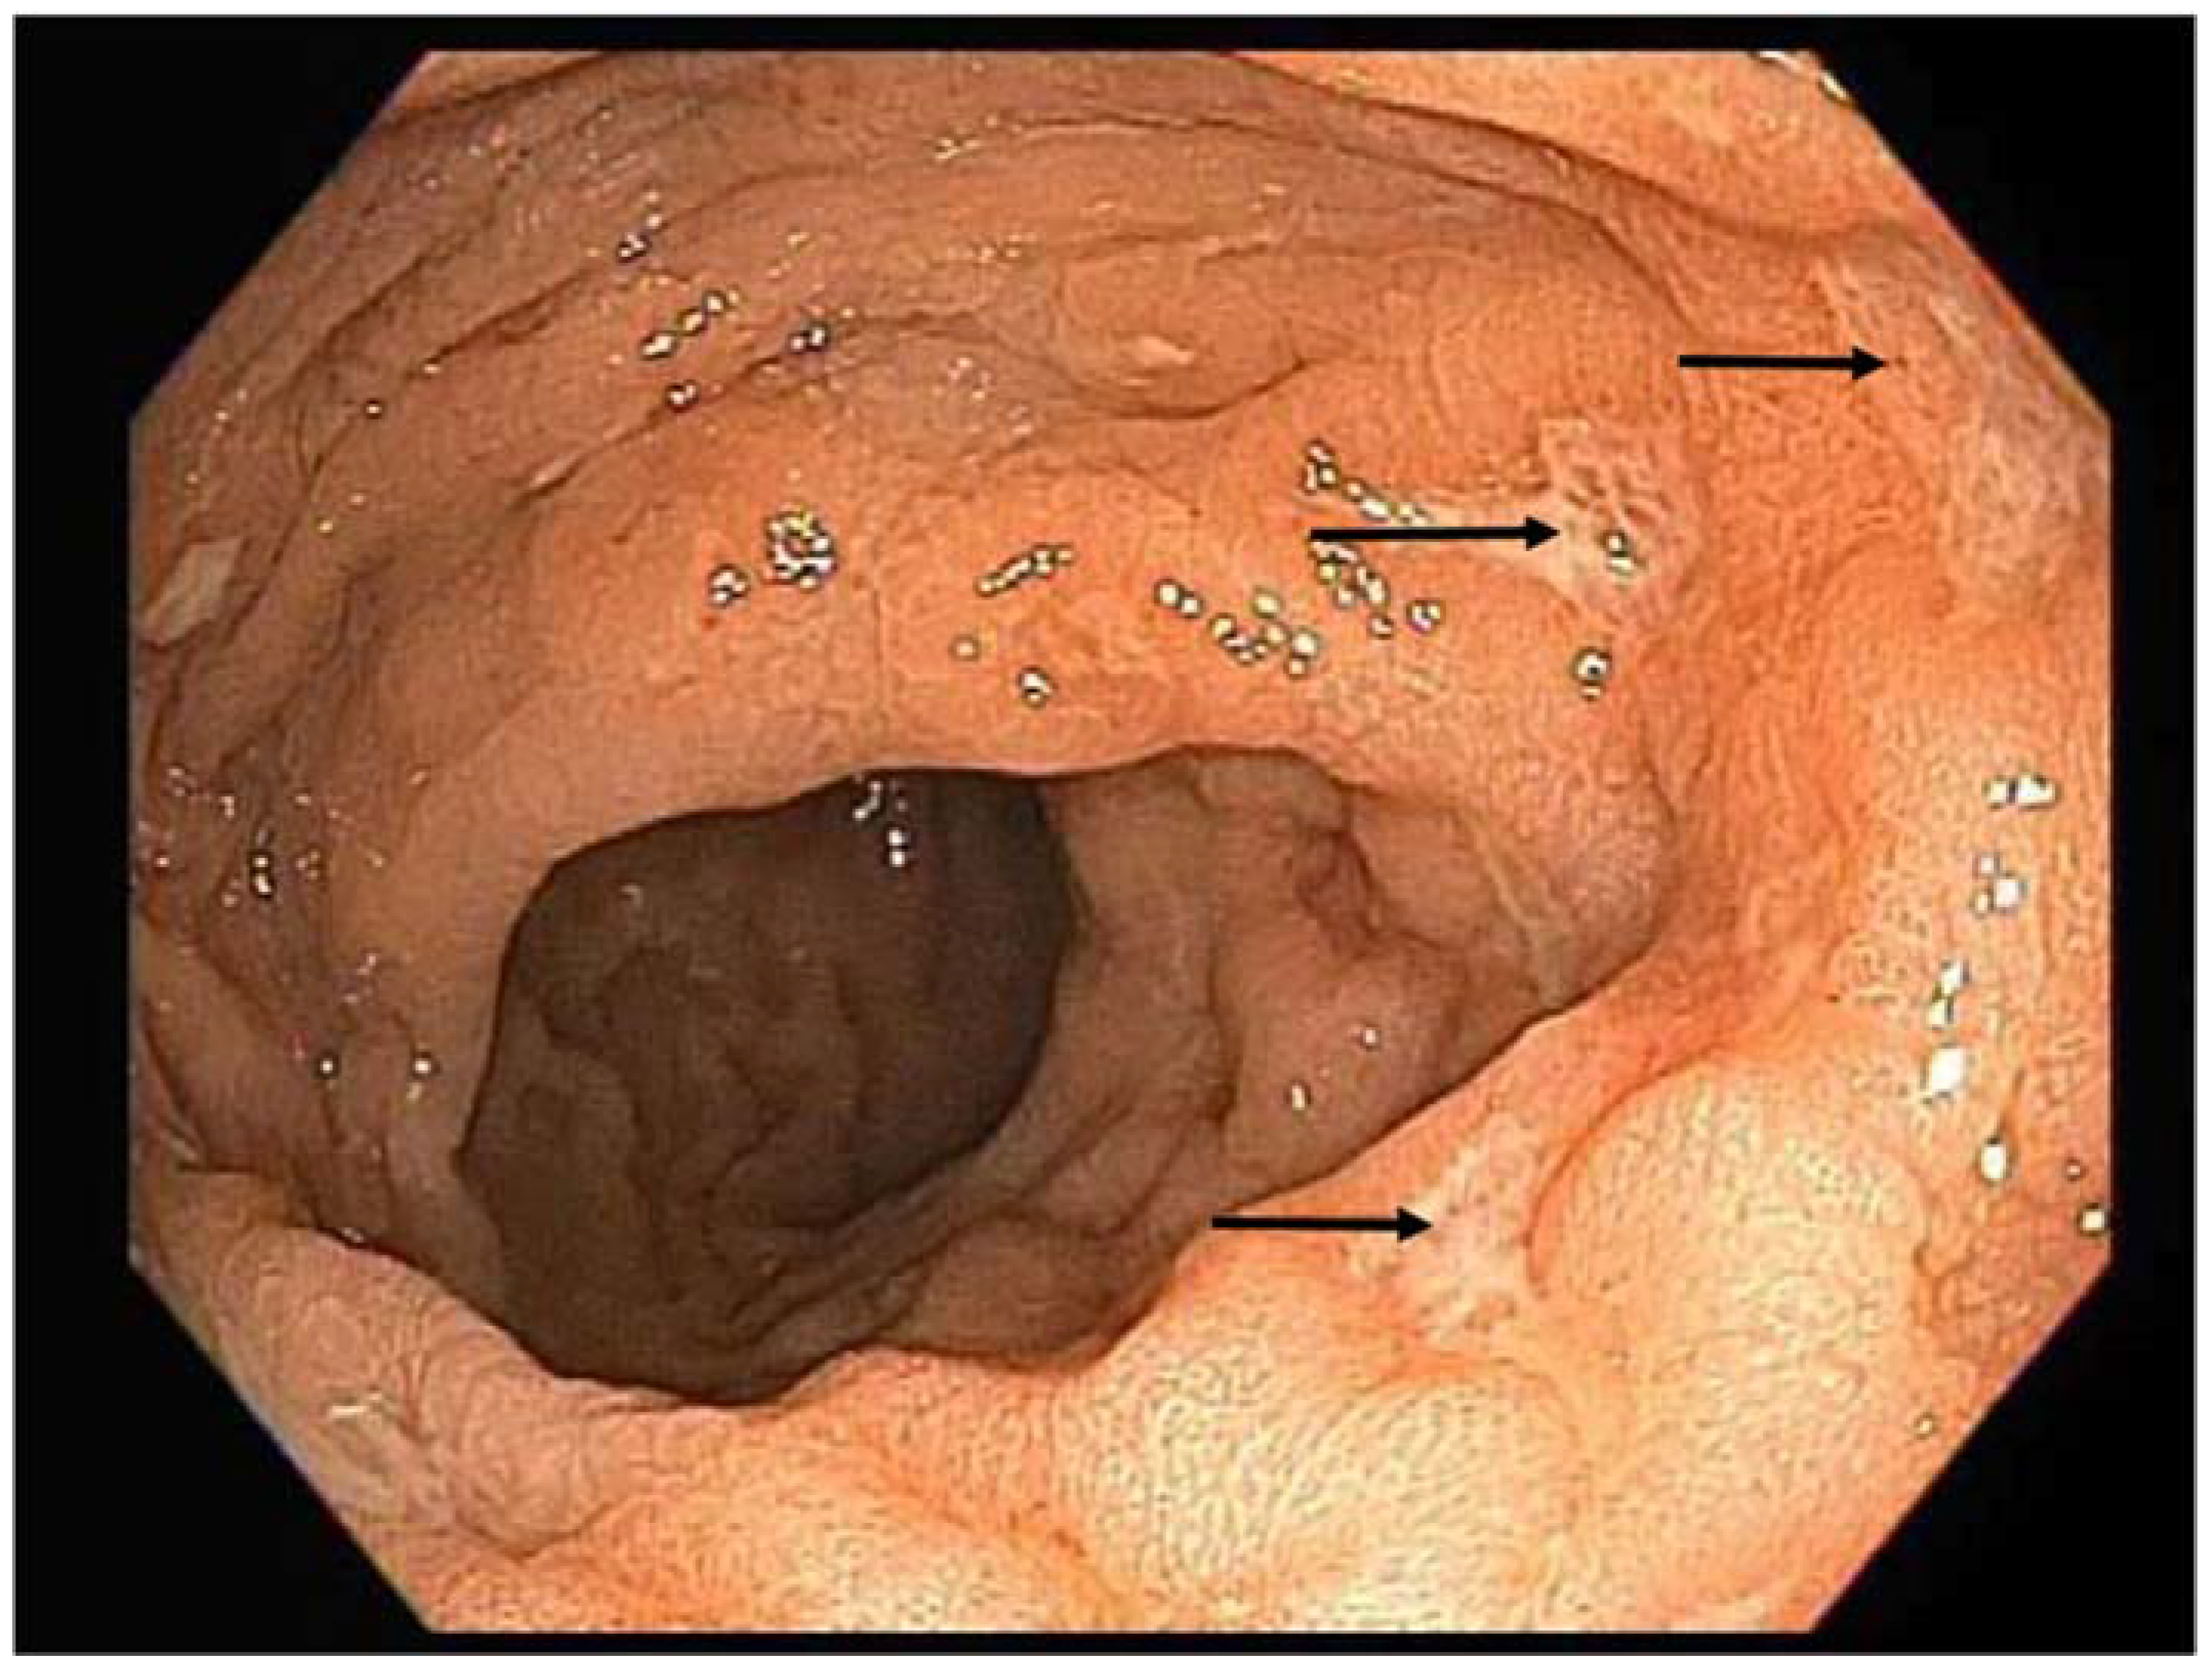

A 48-year-old man originally from Mexico presented to the Infectious Disease clinic with constipation and painful defecation in the last 4 weeks. He had noticed streaks of blood on the toilet paper after wiping. He had a 5-year history of HIV infection treated initially with Tenofovir/emtricitabine/efavirenz that was recently switched to abacavir/lamivudine/dolutegravir. His latest CD4 count was 304 cells/uL and his HIV viral load was undetectable. He was MSM (men who have sex with men), but denied unprotected sex in the last 3 months. His vital signs were within normal limits. He weighed 77.1 kg and did not report any significant weight loss. His abdomen was soft, nontender and non-distended. Bowel sounds were normoactive. Rectal exam was normal. Laboratory studies showed hemoglobin of 14.1 g/dL, leukocyte count of 4.7 K cells/uL and platelet count of 246 K cells/uL. Chemistry panel was significant only for mildly elevated alkaline phosphatase (142 U/L). RPR (rapid plasma reagin) was negative. Stool culture was negative for Salmonella, Shigella, Aeromona and Plesiomona. Campylobacter antigen and Escherichia coli shigatoxins were not detected. Ova and parasites were not isolated in stool studies. He underwent rectal swab for gonorrhea and chlamydia PCR, which gave negative results. Given unrevealing work-up, the patient was referred to Gastroenterology for endoscopic evaluation. Colonoscopy showed moderate inflammation characterized by congestion, erythema and friability of the rectal mucosa. Shallow ulcerations were noted only in the rectum (Figure 1). The rest of the colon did not show any abnormalities. Histopathology examination of rectal tissue disclosed a mucosa with increased lymphoplasmacytic and neutrophilic infiltrate in lamina propia. Acute cryptitis and focal crypt abscesses were noted, along with erosions and few poorly formed granulomas (Figure 2). Immunohistochemistry for HSV1, HSV2, and CMV was negative. Tissue AFB (acid-fast bacilli) staining did not show any organisms. AFB smear in stool was negative; however, two weeks later, stool culture grew Mycobacterium sp. that was further identified as Mycobacterium avium-intracellulare complex by DNA probe. No susceptibility testing was performed. Rectal tissue culture did not grow any organisms. To complete the work-up, a chest X-ray and quantiferon gold were ordered. The results were unremarkable. The patient was started on azithromycin 500 mg daily, rifabutin 300 mg daily and ethambutol 1200 mg daily. At 2-month follow up, the patient reported complete resolution of his symptoms. Four months later, rifabutin was discontinued. The plan was to continue with azithromycin and ethambutol for six additional months to complete a total treatment course of one year.

Figure 1.

Colonoscopy showing shallow ulcerations in rectal mucosa (arrow).